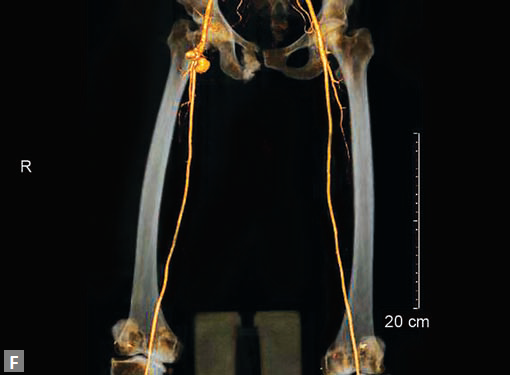

Pseudoaneurysms at femoral access site, arterial grafts are best assessed by CT (Figs 25E to I).

In general assessment of lower limb venous system is not adequate in CT. An AV fistula following a femoral puncture is one common scenario a radiologist comes across. Enhancement of venous structures in early arterial phase including IVC is the first clue. A track between the artery and a vein is generally well seen by the radiologist. Venous malformation is seen as diffuse hypodensity with cystic spaces in soft tissues of upper limb or lower limb. A faint contrast enhancement in delayed scan, characteristic of a low-flow malformation is seen. Enhancement of septa is suggestive of lymphatic malformation and mixed occurrence is not infrequent. In AV malformation, feeder arteries and draining veins are seen. Arteries generally are hypertrophied.

It is constellation of venous and capillary malformation with soft tissue and bone hypertrophy of limb. Persistent lateral marginal vein is an association. CT demonstrates bone hypertrophy with length discrepancy in lower limbs, hypertrophy of subcutaneous fat and muscles. Superficial venous varicosities, hypoplasia, aplasia, stenosis and dilation of deep veins are the accompanying features. Persistent lateral margin vein is the most common type of fetal veins. When the deep veins are dysplastic, extensive varicectomy is not performed.